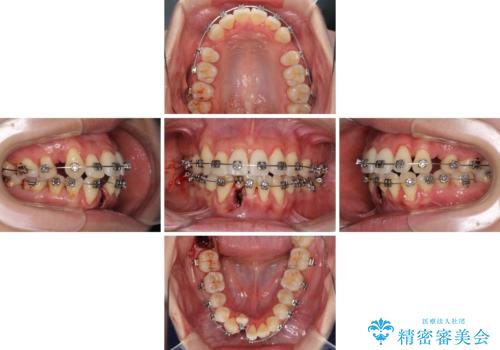

- メタルブラケット

- 2年8ヶ月

- 10-30回

通常であれば、上下顎左右小臼歯各1歯の合計4本を抜歯しますが、歯肉退縮の著しい下顎前歯を抜歯して欲しいという患者様の強い希望により、上顎のみ左右小臼歯2歯を、下顎は前歯を1歯を抜歯することとしました。

抜歯する歯を変更したため奥歯の咬合はアンバランスとなりましたが、前歯は綺麗に整い、歯肉退縮も回避できました。